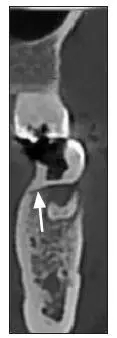

患者,女,42歲,因牙痛就診于中南大學(xué)湘雅醫(yī)學(xué)院附屬??卺t(yī)院牙體牙髓病科。臨床檢查為左側(cè)下頜第一磨牙遠(yuǎn)中齲,根尖壓痛和扣痛及頰側(cè)深牙周袋,牙髓電活力檢查陰性,近中根尖放射透明影。X線檢查根分叉區(qū)有不透明突起,扁形,

1.8 mm寬、8 mm長(zhǎng)(圖1~3)。

圖 3 CT頰舌切面觀

Fig 3 CT buccolingual section view